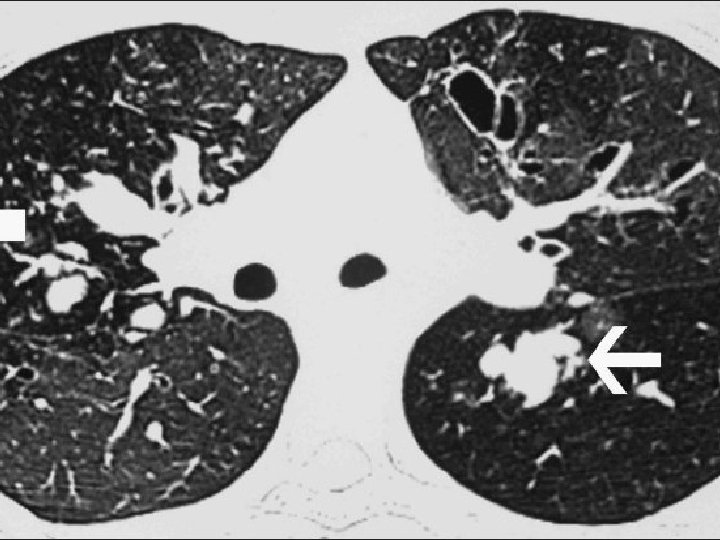

Case: Diagnosis Exacerbation after ingestion of aspirin or other non-NSAIDs Starts with intractable nasal congestion and watery rhinorrhea Refractory to pharmacologic Treatment Progressive, may become associated with anosmia Specific Ig. E tests negative Nasal polyposis Total or near-total opacification of the sinus cavities (on CT) An individual with rapid onset of a severe attack with no previous insult who necessitates acute emergency care, intensive care unit admission, or endotracheal intubation